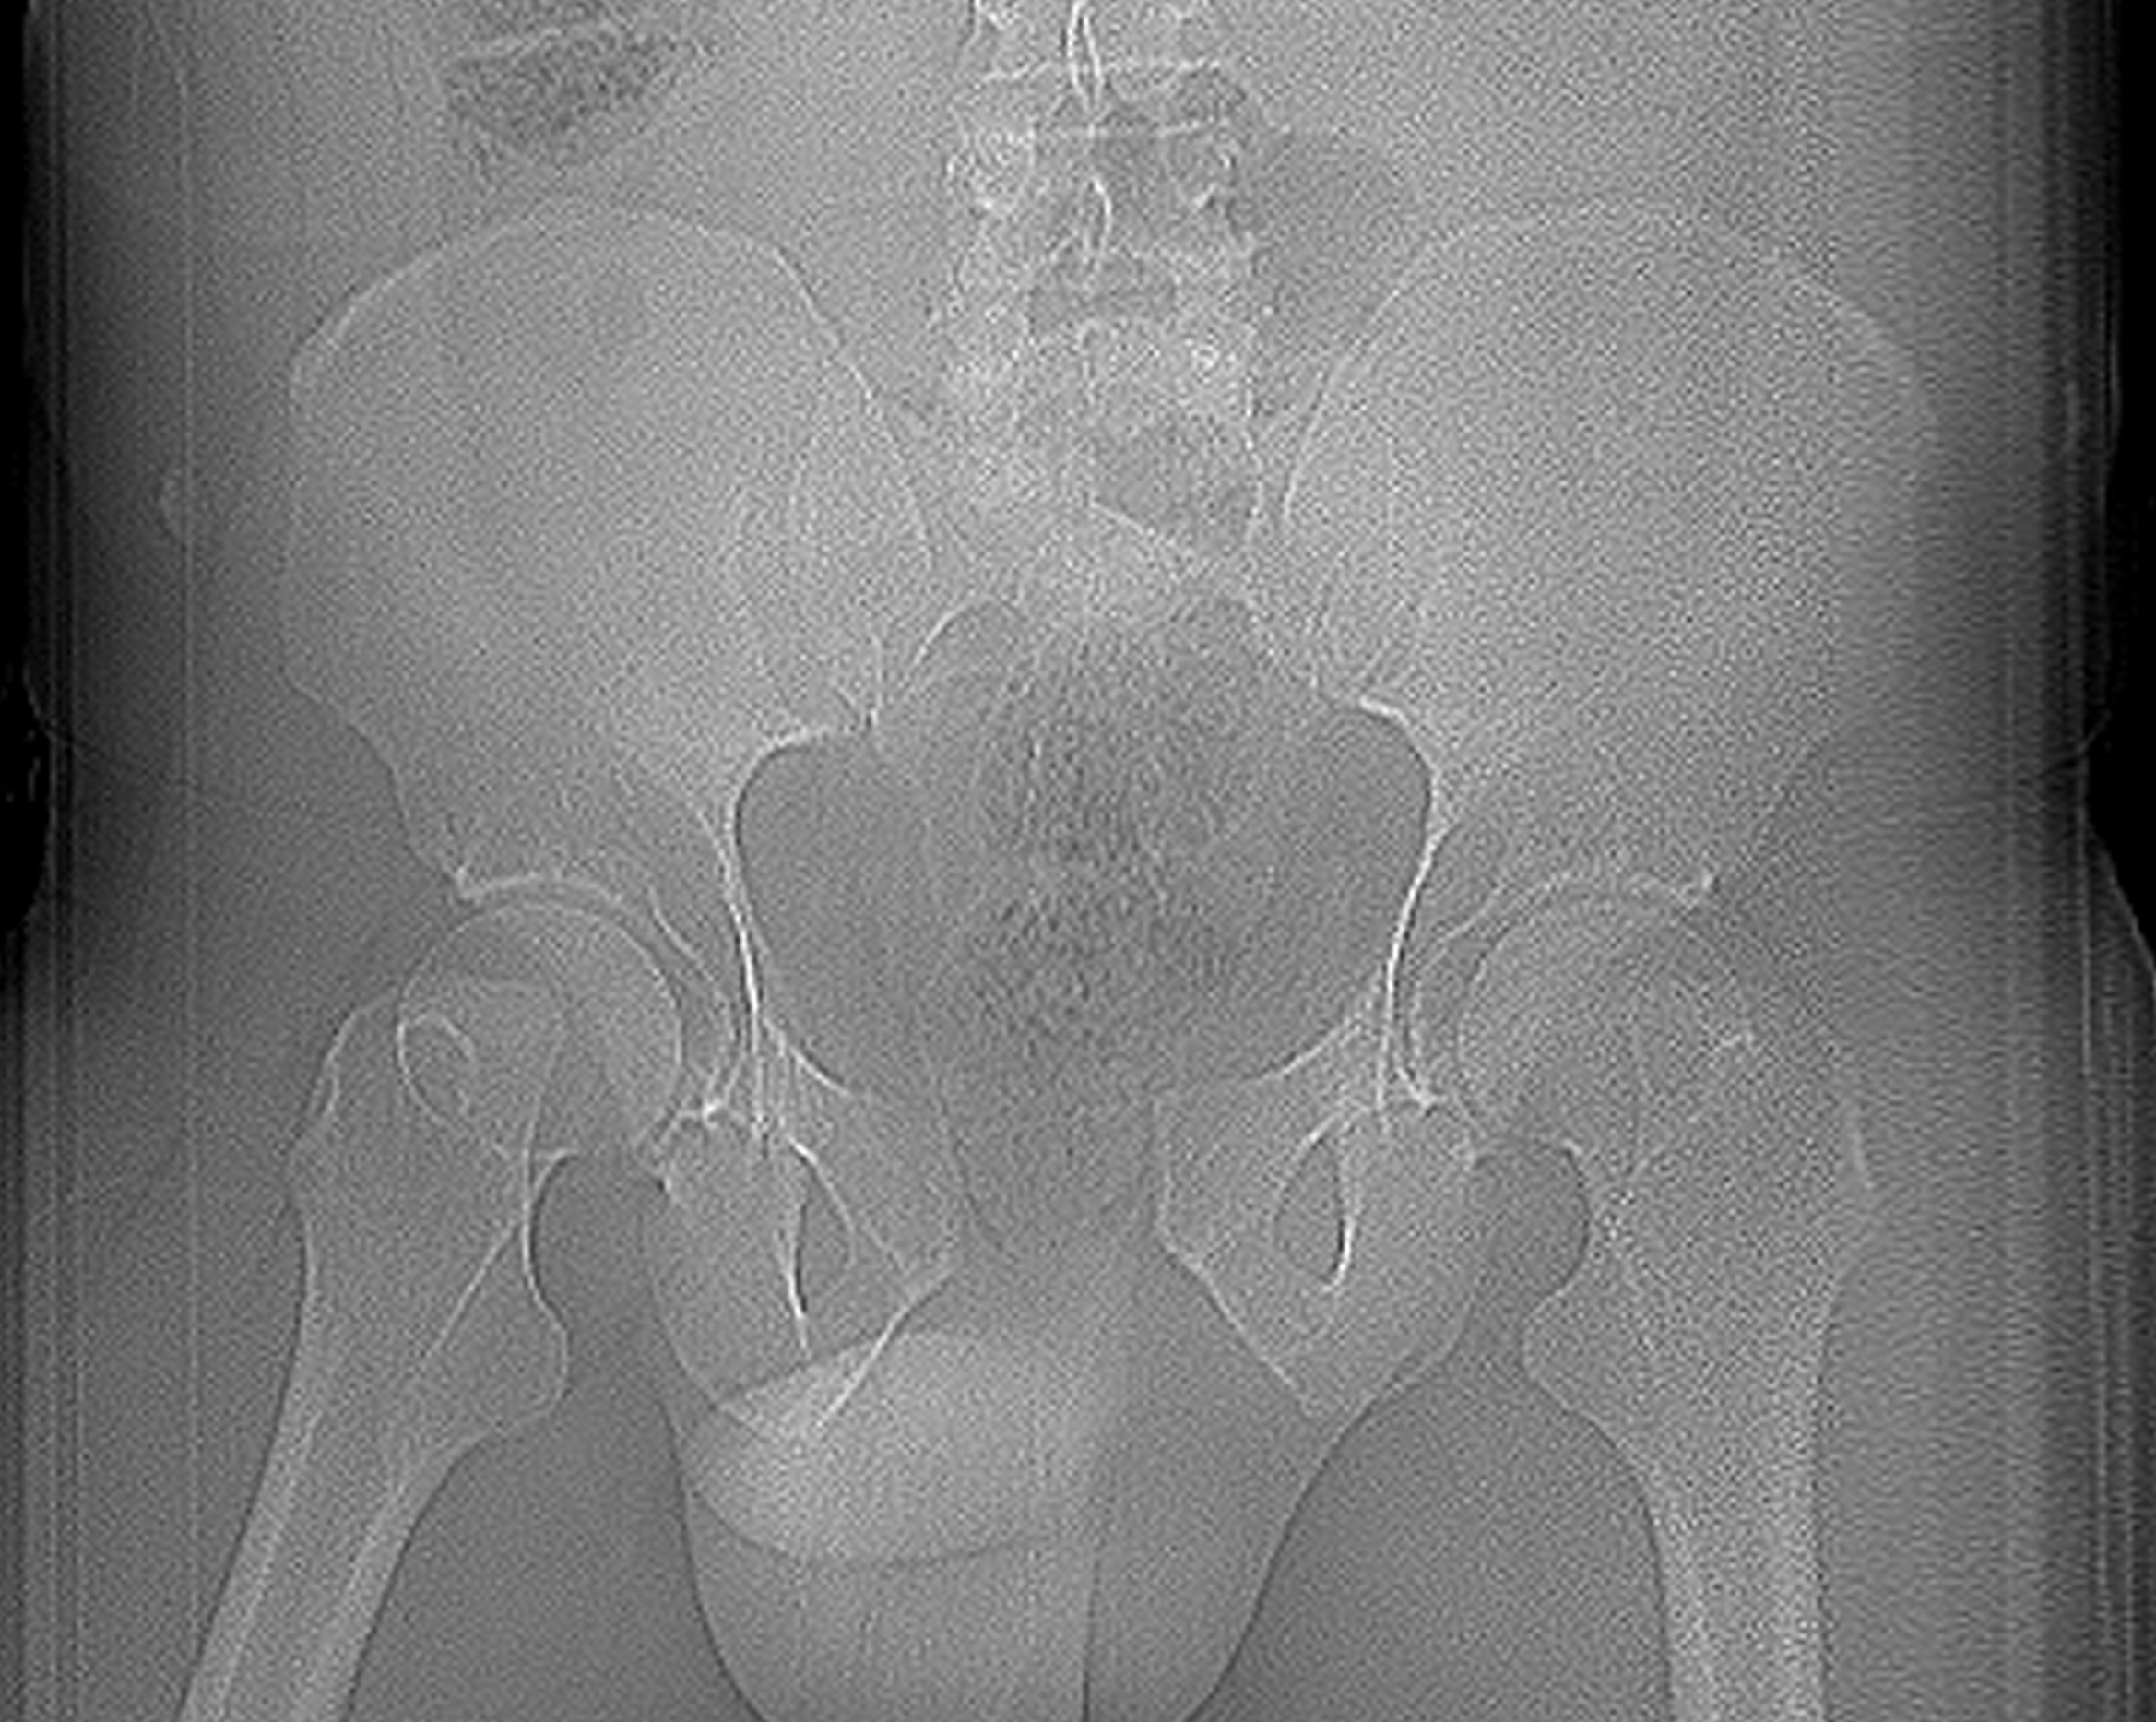

X-rays

Inlet view

- 40o caudal

- shows AP displacement of sacrum and anterior ring

- anterior and posterior sacral borders

Pelvis Inlet viewPelvis Inlet

Outlet view

- 40o cephalad

- vertical displacement of sacrum relative to ilium

Pelvis Outlet ViewPelvis Outlet